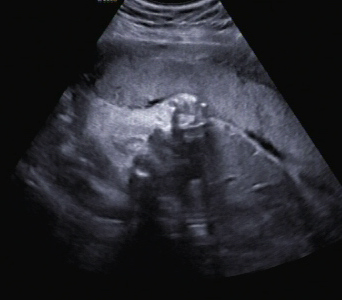

Ein zunächst durchgeführtes CTG war unauffällig. Im Rahmen der sonografischen Untersuchung zeigte sich der Fötus soweit beurteilbar zeitgerecht entwickelt. Dennoch konnte ein Anhydramnion festgestellt werden(Abb. 1, 2), weshalb auch kein fetales Gesicht darstellbar war (Abb. 3).